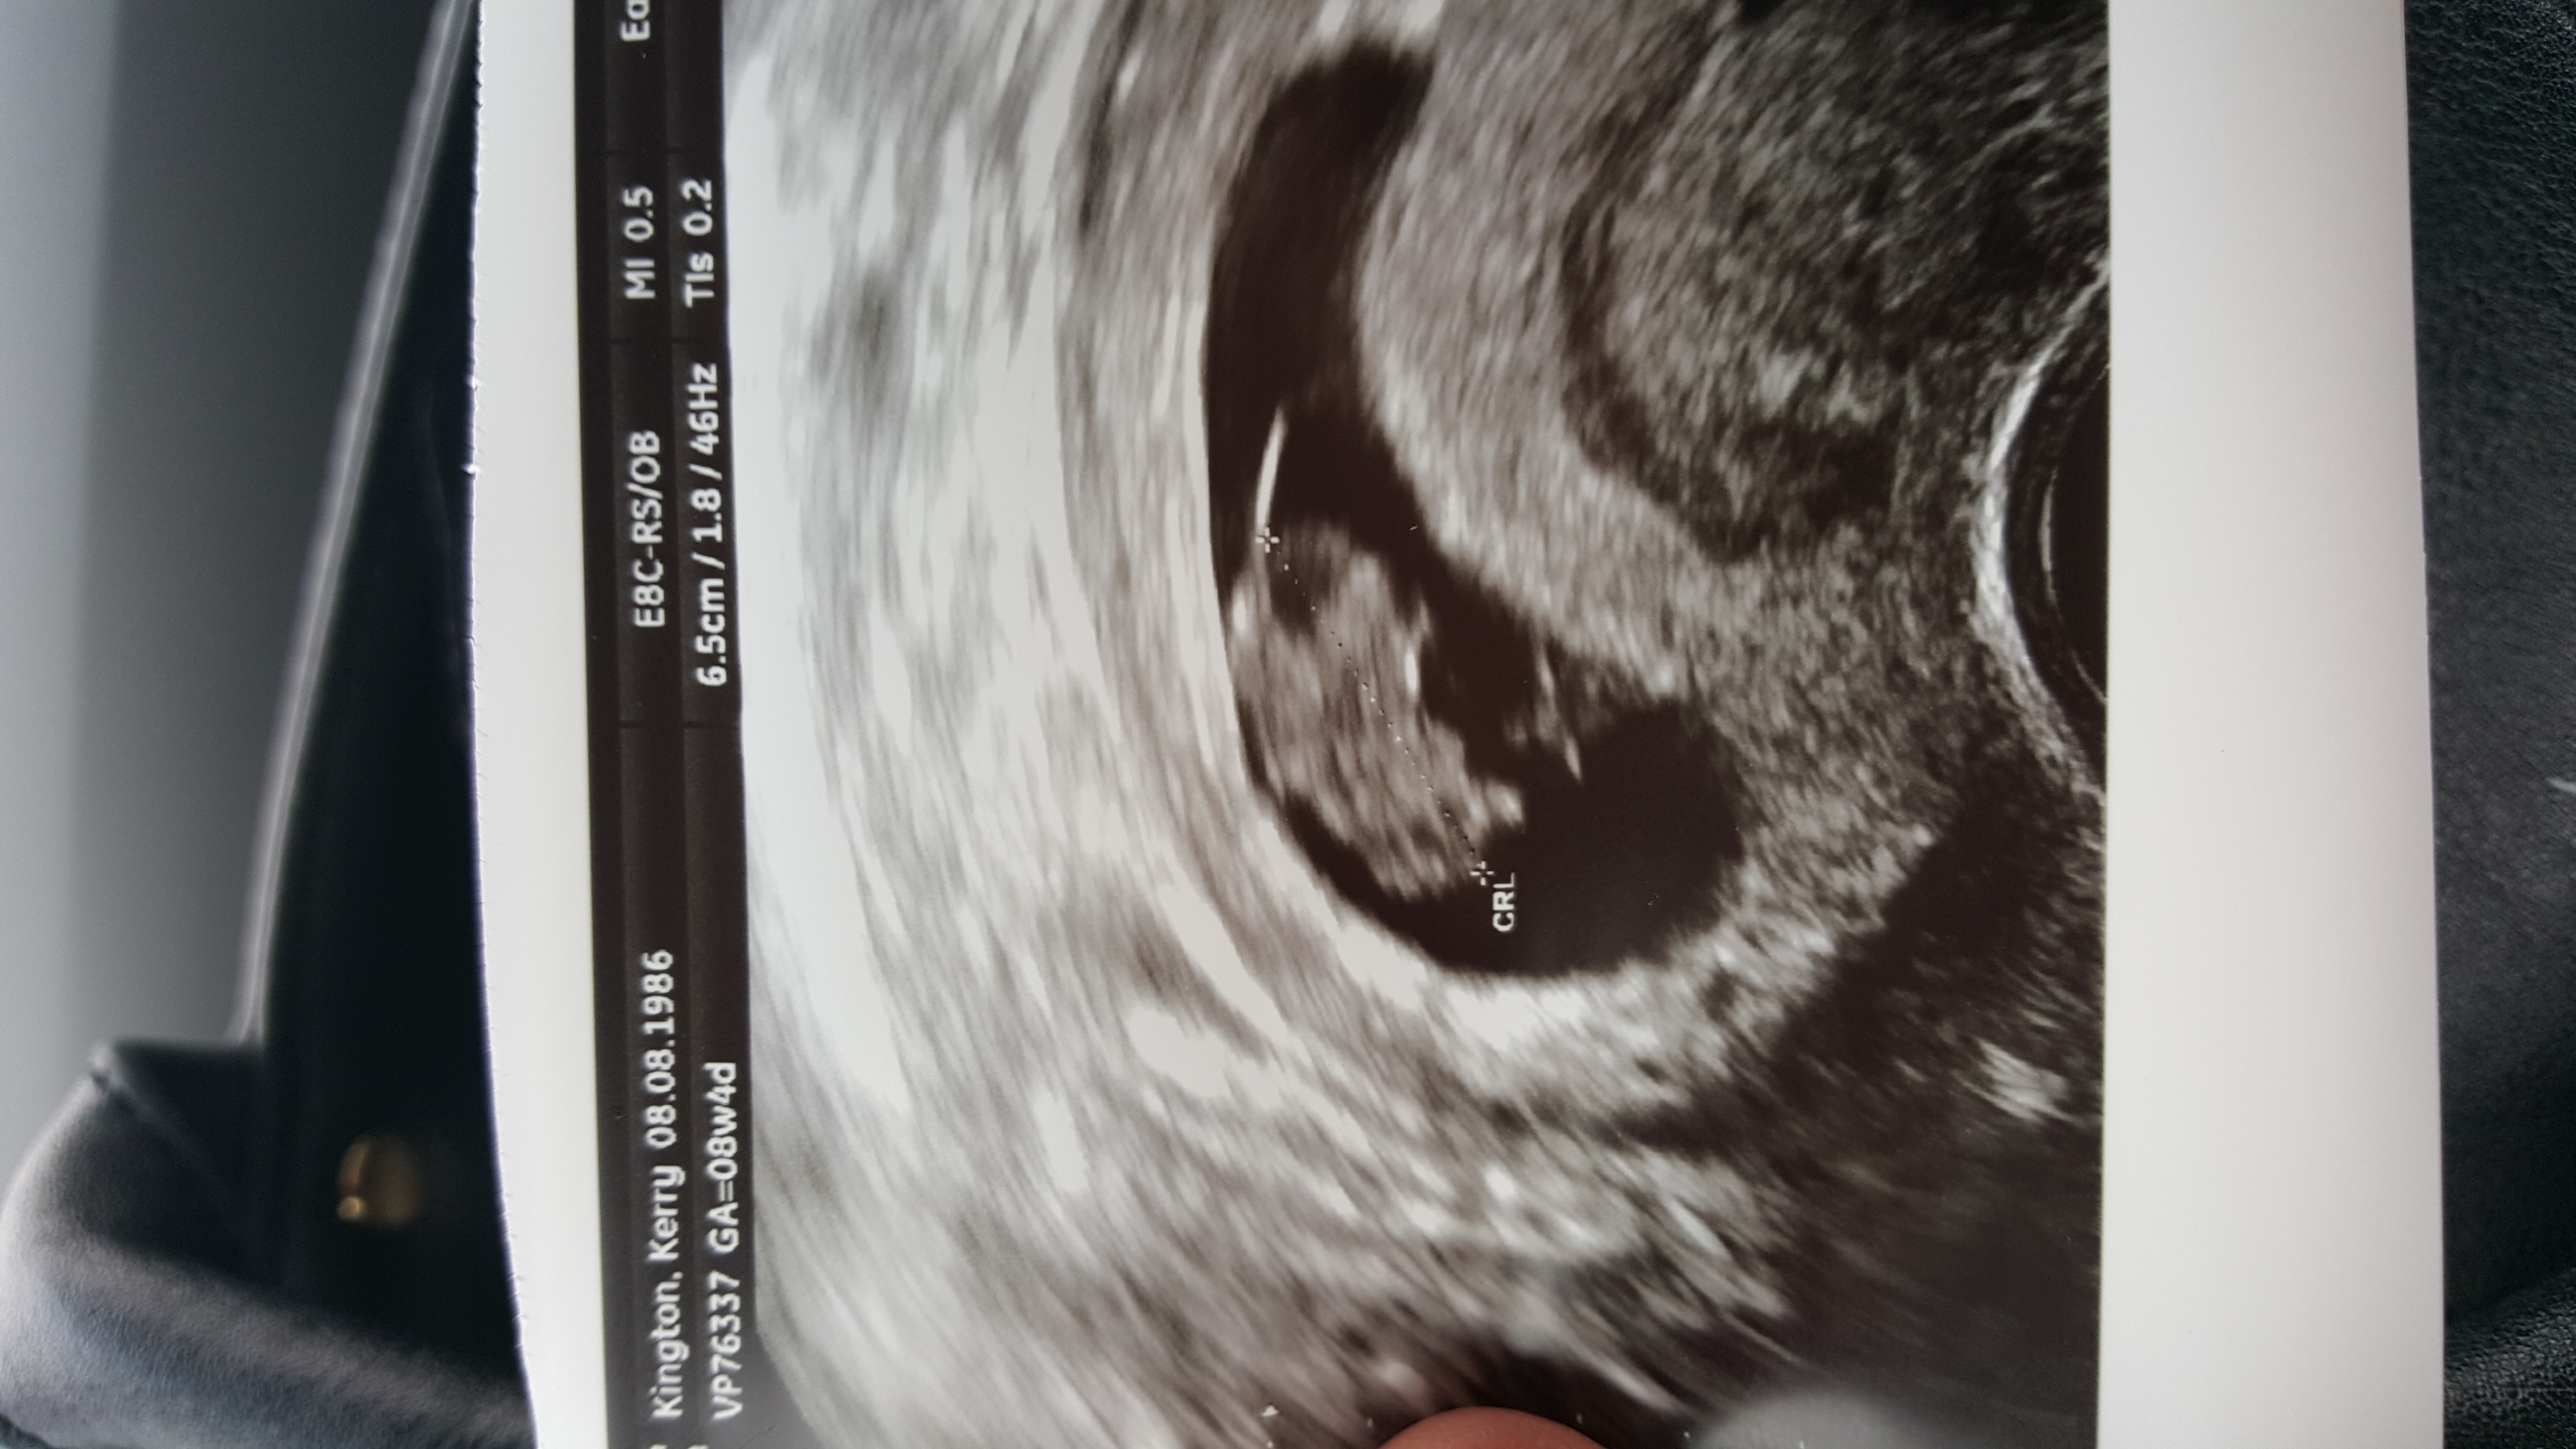

Here we are!!! I've been so excited to post this. My rainbow baby at 8w2d. Measured exactly as we thought with 165bpm. Baby looks a bit like a Lego character so I'm picturing "everything is awesome" playing on repeat as baby grows!!! Due April 13!

• Yay I can put one here! I had my ultrasound yesterday. I measured 7w4d and the heartbeat was 162! Here's a pic of my little bean!

• 7.5 weeks! The next is at 12 weeks.

• I have another ultrasound picture to share! Last time we were around 7 weeks, here I'm 8w6d!!! It was a crappy old machine, but she guessed the heartbeat was about 160 and we got to hear it again!!! So so so happy! For all you ladies that have symptoms that come and go, here's some hope for you because everything was fine even though my nausea and sore boobs have mostly stopped. Good luck!!!

• I am 7 weeks today and after doing 9 tests I think it is sinking in. :) I've had 2 losses in the past and also my gorgeous 5 year old boy in-between. Worried because it's been so long since I had a successful pregnancy so I have booked a scan for this Friday coming. Has anyone else had one at 7 weeks 5 days and what could you see? Want to know what I can expect lol x

• I have had two one at 6 weeks and one at 8 weeks there is such a difference!